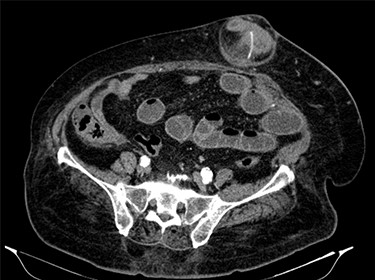

Fluid resuscitation measures, monitoring of urine output and pain control were initiated. Analytically, she had leukocytosis of 227 000/μl with neutrophilia 89%, elevated C-reactive protein 27.1 mg/dl and acute kidney injury with creatinine 1.8 mg/dl and urea 96 mg/dl. Arterial blood gas analysis showed no acidosis, respiratory failure or hyperlactatemia. The computed tomography (CT) scan identified an umbilical hernia containing a small bowel loop, evidenced densification of the hernia fat and some bubbles of extraluminal gas were also present (Fig. 2). An image of high-density and filiform morphology compatible with an FB (Fig. 3) was also identified. Images were consistent with dilation of the proximal intestinal loops, which suggested bowel occlusion.

Abdominal CT: image of high-density and filiform morphology compatible with FB.